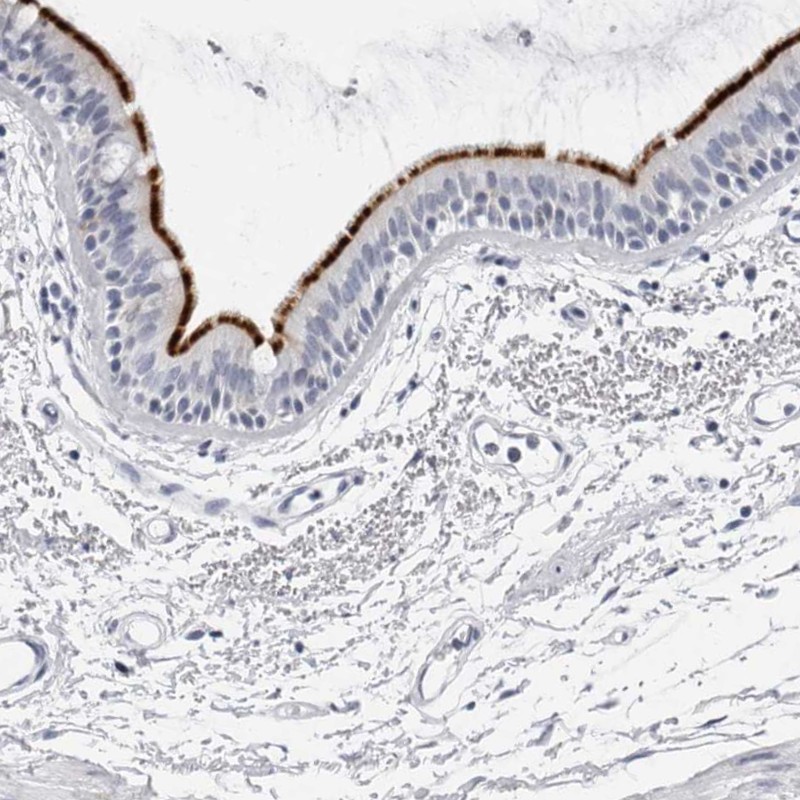

Immunohistochemical staining of human bronchus shows strong membranous positivity in respiratory epithelial cells.